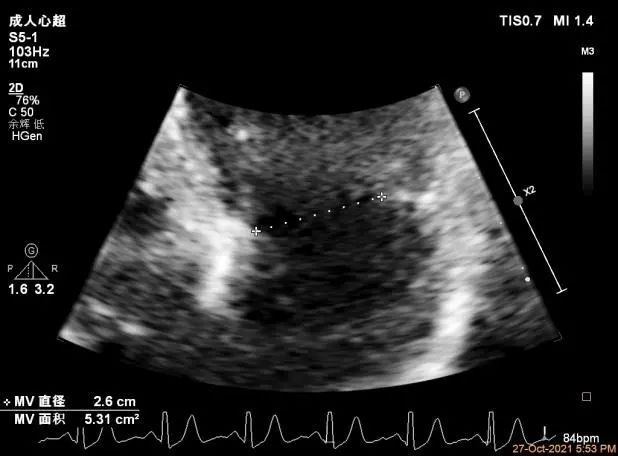

二尖瓣瓣环前后径26mm,左右径26mm

Qlab软件勾画估测瓣口面积约:5.6cm²

二尖瓣口平均跨瓣压差:4mmHg